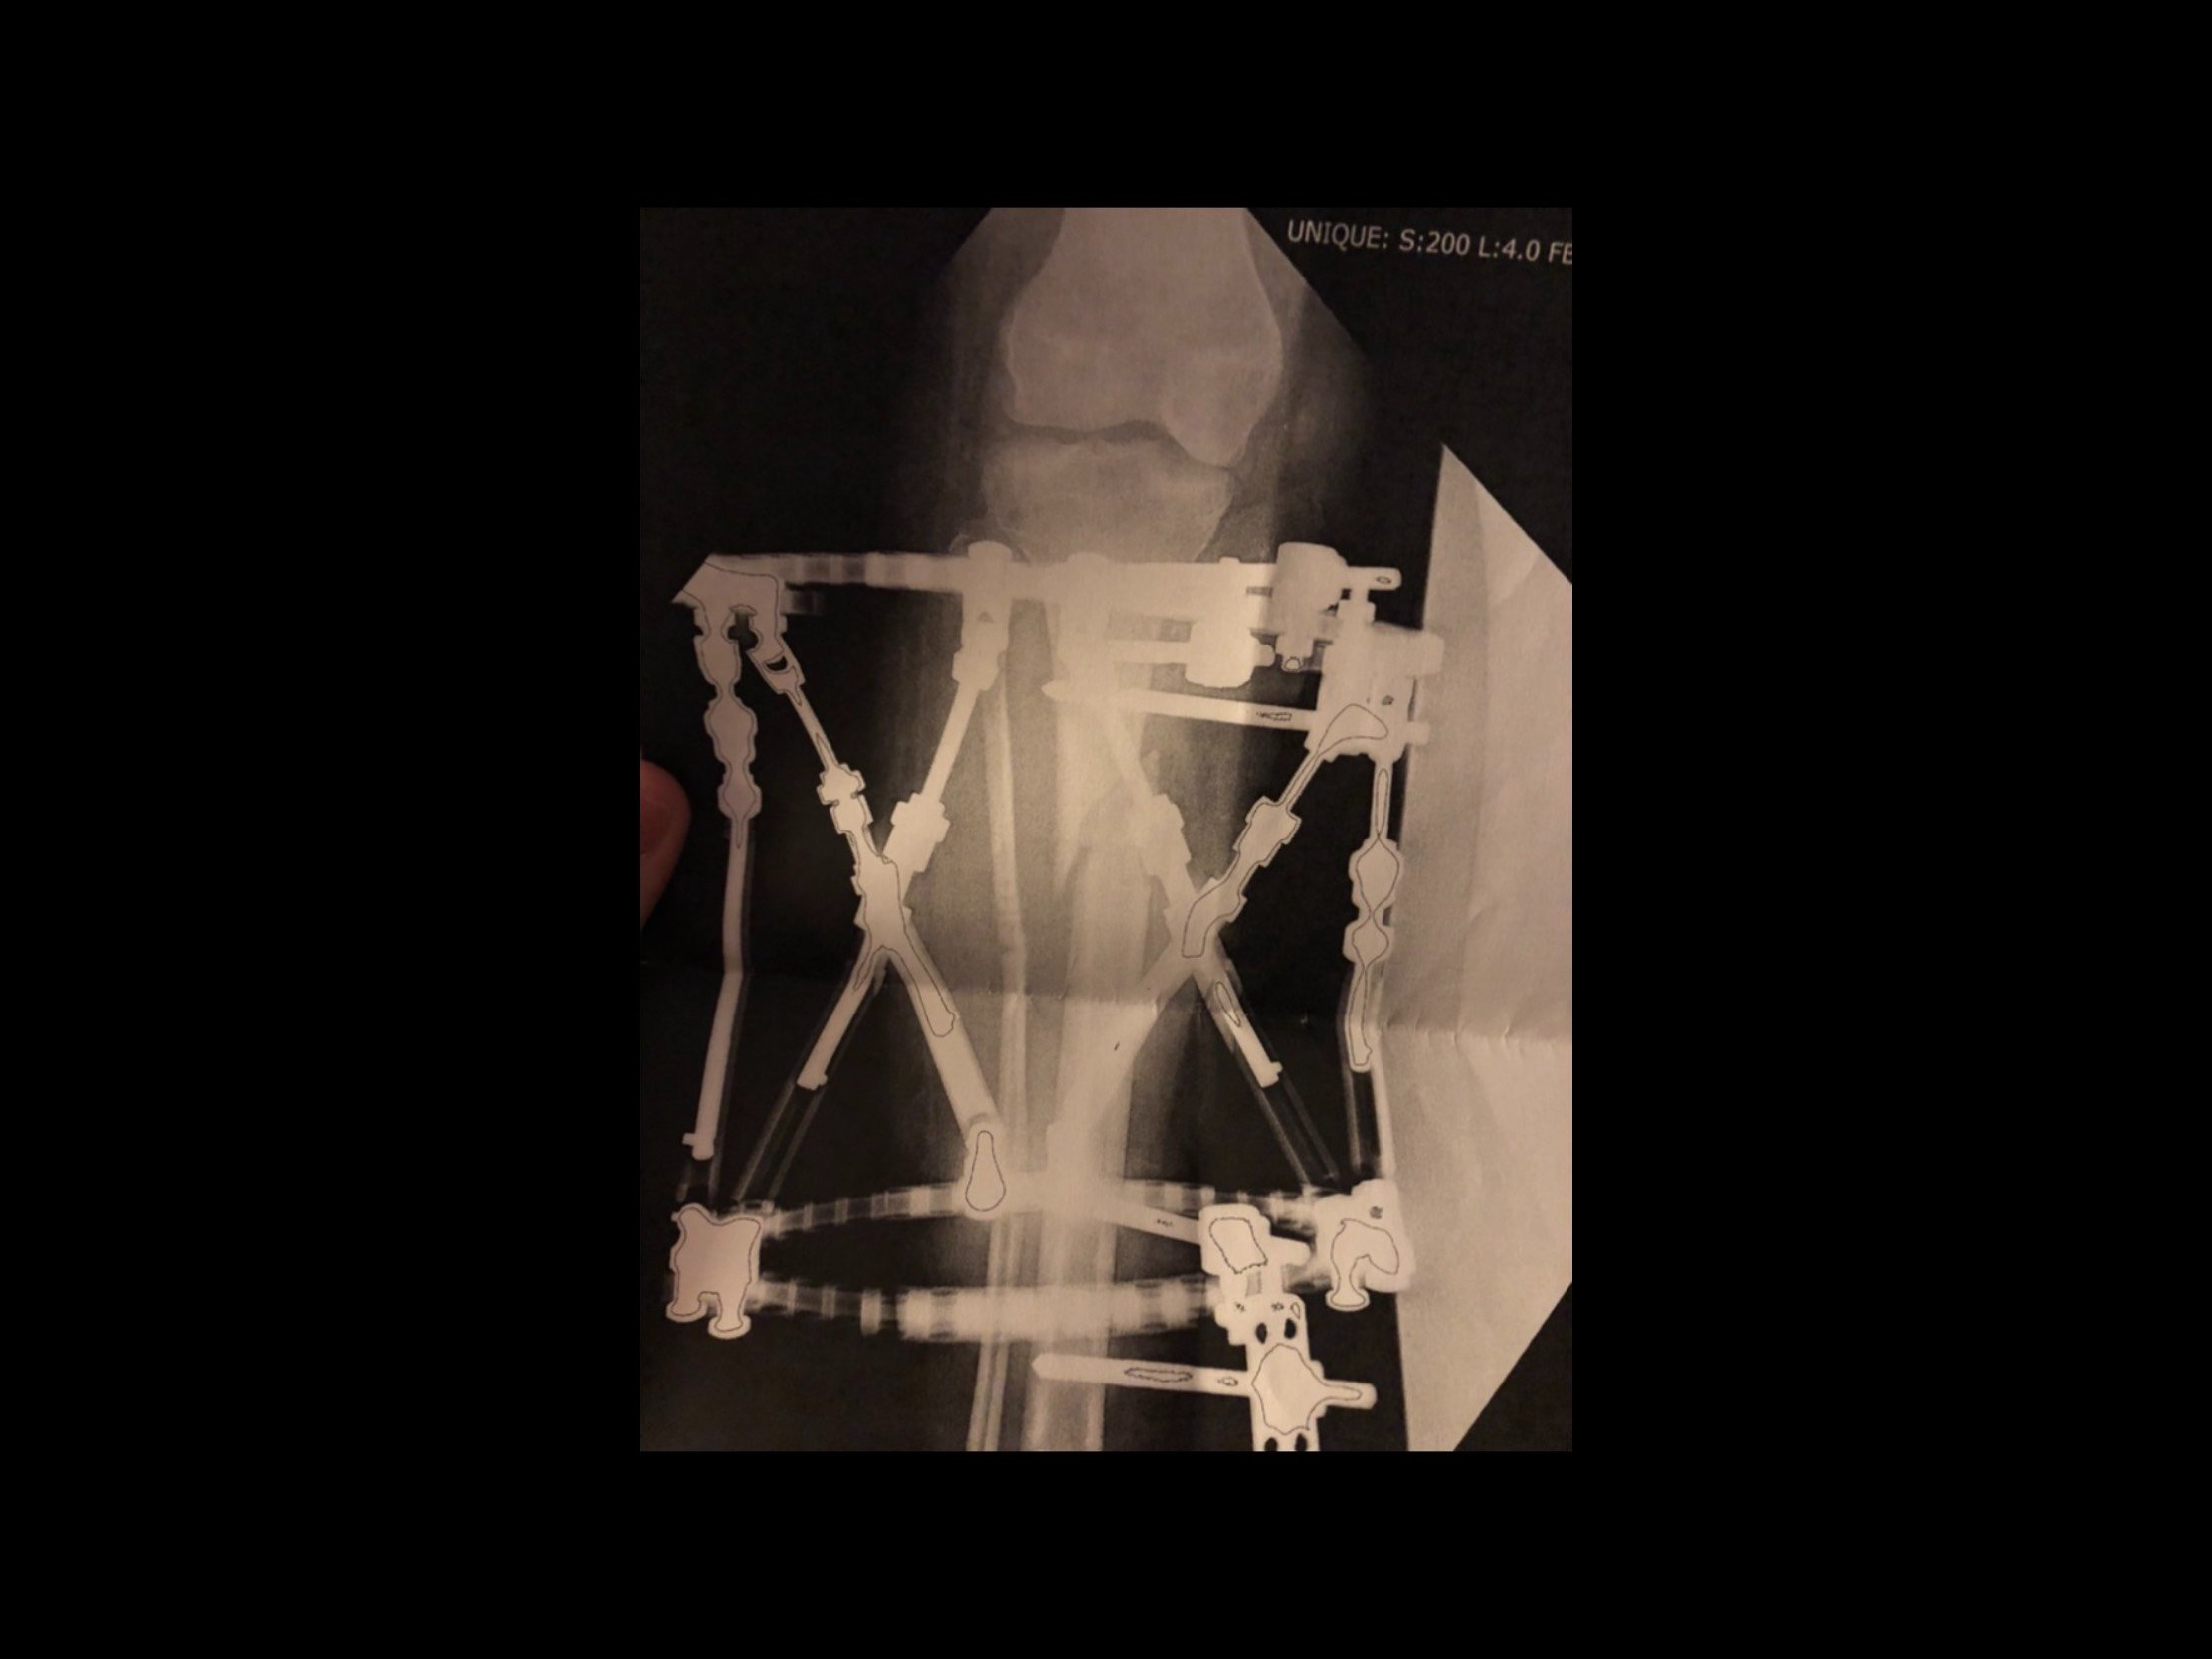

Then came the big one. I’ll share more in a separate post, but the short version is: I re-injured my ankle just going through daily life. We eventually found out my tibia had 47 degrees of torsion. That explained why my ankle kept tearing—it was being pulled in the wrong direction.

I had a combined surgery where they cut and realigned my tibia, repaired the ankle, and placed an external fixator (rods outside my leg that held the bone together during healing).

It was a long, complex recovery that changed the trajectory of my career and life.